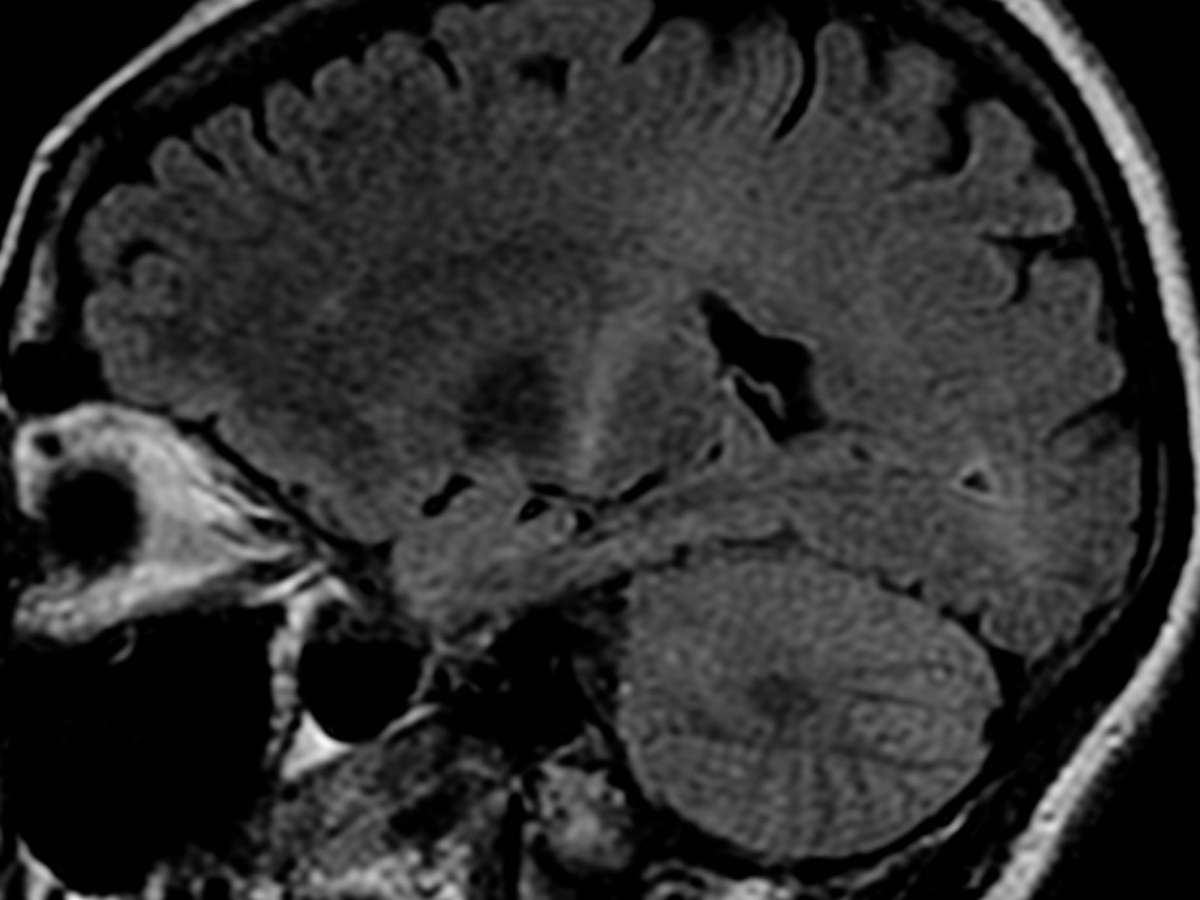

Portadores de Esclerose Lateral Amiotrófica (ELA) estão sem receber o medicamento Riluzol

Foto: Wikipédia